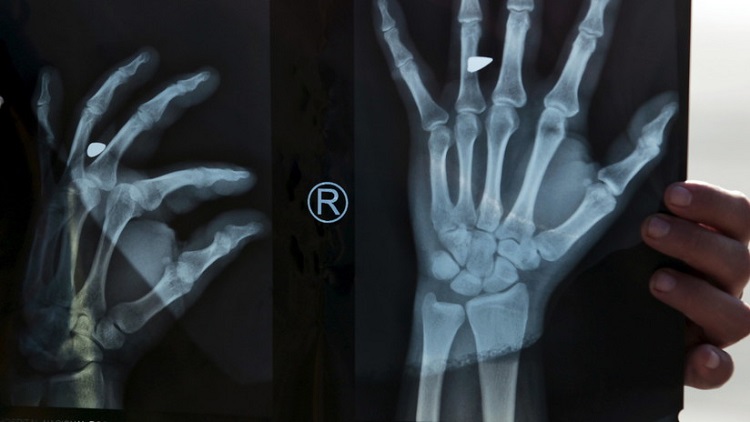

El traumatólogo que la atendió descubrió que el dedo estaba hinchado y de color púrpura oscuro. La razón: los médicos que la operaron habían olvidado retirar un torniquete elástico usado durante la cirugía. Tal descuido había provocado la interrupción del flujo sanguíneo y, en consecuencia, una seria necrosis en la zona.

Finalmente, un cirujano decidió amputar el segmento afectado y reemplazarlo con el dedo gordo del pie de la propia paciente. De manera consecuente, le crearon un hueso nuevo a partir de un trozo de cadera para sustituir el apéndice inferior.